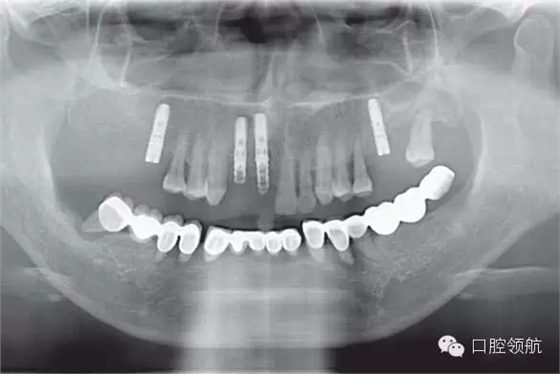

下頜為十數(shù)年前制作的三組金屬烤瓷橋修復(fù)體。右下4、5、7帶缺失的6;右下3、1及左下1、2帶缺失的右下2;左下3、4、5、8帶缺失的6、7,左下8修復(fù)后牙齒自然脫落,全景片無左下8的影像。幾乎所有的余留牙周圍的骨質(zhì)均吸收到根尖1/3。臨床上三組下頜金屬烤瓷橋均有較大幅度的松動(圖6-7,圖6-8)。

圖6-8 下頜術(shù)前全景片